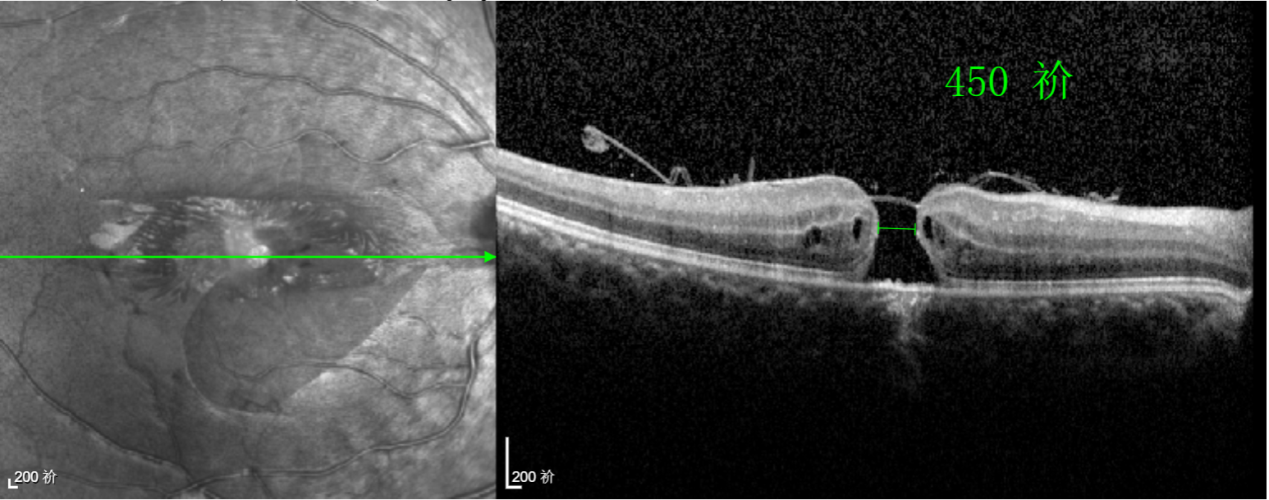

經(jīng)過(guò)詳細(xì)的檢查和評(píng)估,王曉波主任決定采用“內(nèi)界膜翻轉(zhuǎn)覆蓋聯(lián)合粘彈劑固定術(shù)”為誠(chéng)誠(chéng)進(jìn)行治療。

術(shù)中,醫(yī)生精細(xì)剝離黃斑區(qū)的內(nèi)界膜后,并非直接丟棄,而是巧妙地給它翻個(gè)面,讓它變成一塊天然“創(chuàng)可貼”,嚴(yán)密覆蓋在黃斑裂孔的表面。覆蓋的內(nèi)界膜像微型支架一樣撐住裂孔邊緣,防止它擴(kuò)大;同時(shí),這層膜本身含有能促進(jìn)生長(zhǎng)的“養(yǎng)分”,能顯著刺激裂孔周圍的視網(wǎng)膜組織像爬山虎一樣快速生長(zhǎng)、蔓延過(guò)來(lái),最終把裂孔“補(bǔ)”好。

王曉波主任表示:該術(shù)式無(wú)需依賴硅油或氣體去頂壓裂孔促進(jìn)愈合,術(shù)后也就無(wú)需再保持俯臥體位,這不僅極大提升了患者的舒適度,更顯著提高了治療依從性。對(duì)于活潑好動(dòng)的兒童、難以長(zhǎng)時(shí)間保持特殊體位的老年人,以及因其他健康問(wèn)題無(wú)法耐受俯臥的患者而言,這項(xiàng)技術(shù)無(wú)疑帶來(lái)了巨大的便利和改善。

除此之外,利用自體組織覆蓋為黃斑裂孔提供了理想的愈合環(huán)境,裂孔閉合速度顯著快于傳統(tǒng)方法。誠(chéng)誠(chéng)接受手術(shù)24小時(shí)后,檢查可見(jiàn)內(nèi)界膜瓣位置良好;術(shù)后1個(gè)月,黃斑裂孔已經(jīng)閉合,視力恢復(fù)到0.5;術(shù)后兩個(gè)月,視力進(jìn)一步提升到0.7。